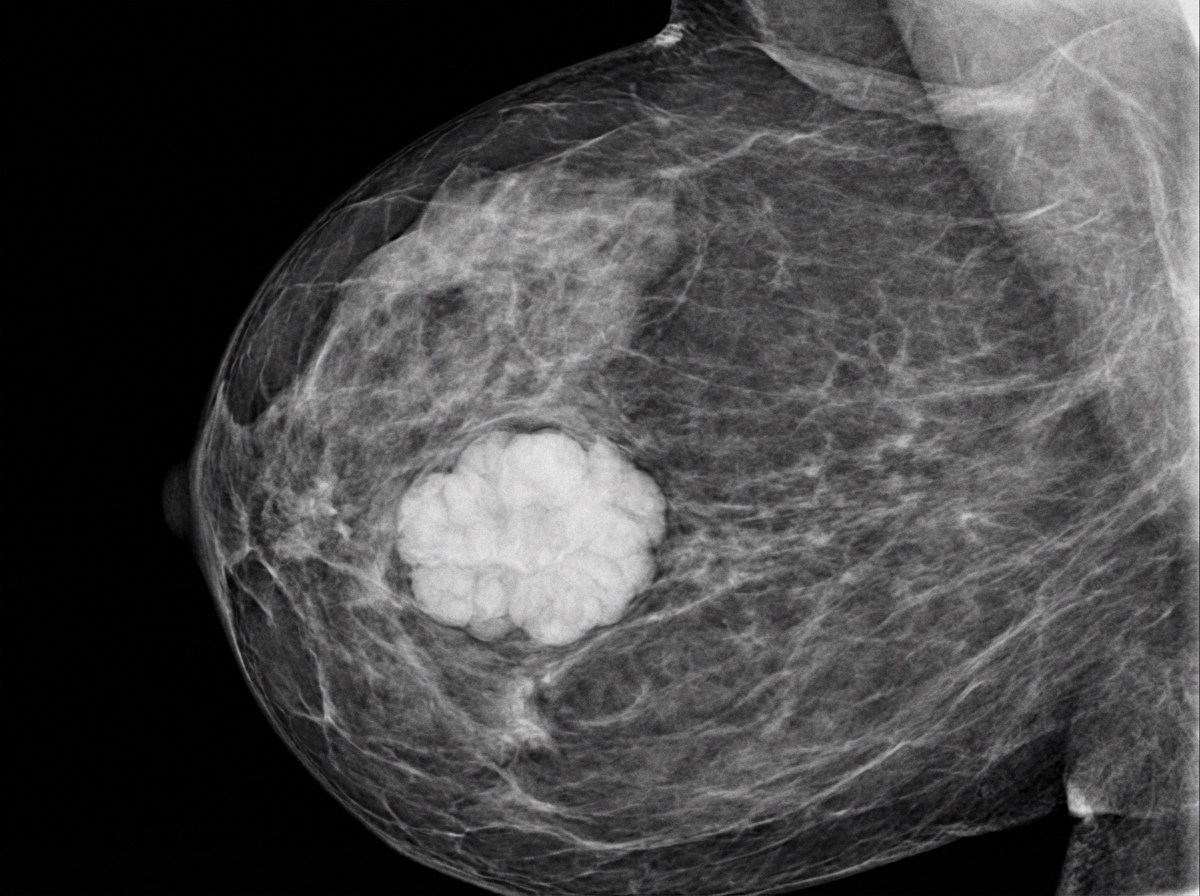

A 39-year-old female presents to her gynecologist complaining of a breast lump. Two weeks ago, while performing a breast self-examination she noticed a small firm nodule in her left breast. She is otherwise healthy and takes no medications. Her family history is notable for a history of breast cancer in her mother and maternal aunt. On physical examination, there is a firm immobile nodular mass in the superolateral quadrant of her left breast. A mammogram of her left breast is shown. Genetic analysis reveals a mutation on chromosome 17. This patient is at increased risk for which of the following conditions?